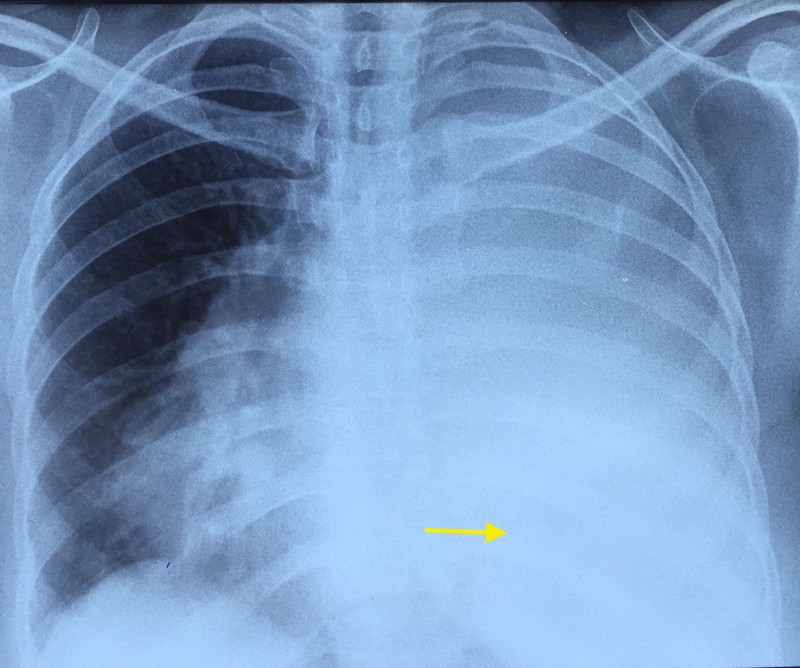

A fifty-year-old woman presented with symptoms of three months’ duration of a dry cough, left-sided chest pain and progressive breathlessness. She was previously evaluated with a chest radiograph (CXR) which showed a left-sided large effusion (figure 1) and was empirically treated with anti-tuberculosis therapy (ATT) with no relief of chest pain.

Chest X-ray showing gross left-sided pleural effusion